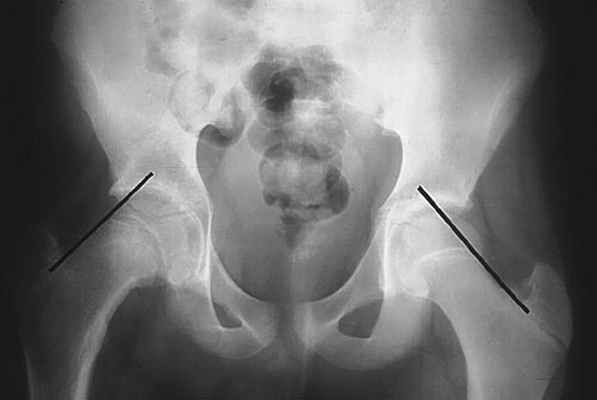

Поскольку вылечить запущенную стадию смещения трудно, ранняя диагностика эпифизеолиза головки бедренной кости является жизненно важной. Проводят передне-задний и латеральный – в положении лягушачьих ножек – рентген обоих бедер. Рентген выявляет расширение эпифизарных линий или очевидное заднее и нижнее смещение головки бедренной кости. Чтобы определить смещение, на рентгеновском снимке на верхней границе шейки бедра наносятся линии Клейна. Головка бедренной кости будет находиться ниже линии Клейна на пораженной стороне, в то время как на здоровой стороне значительная часть головки бедренной кости будет расположена выше линии Клейна.